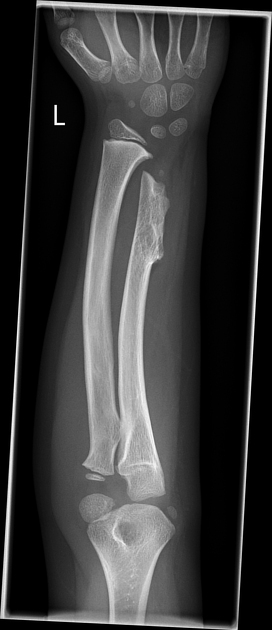

What is the Madelung deformity?

Madelung deformity is caused by epiphyseal growth plate disturbance at the ulnar side of distal radius, resulting in a short radius compared with the ulna.

Features of Madelung deformity

1. Shortening and bowing of radius bones causing dorsal subluxation of the distal radioulnar joint.

2. V-shaped proximal carpal row

3. positive ulnar variance.

4. pisiform can impacted against the ulna